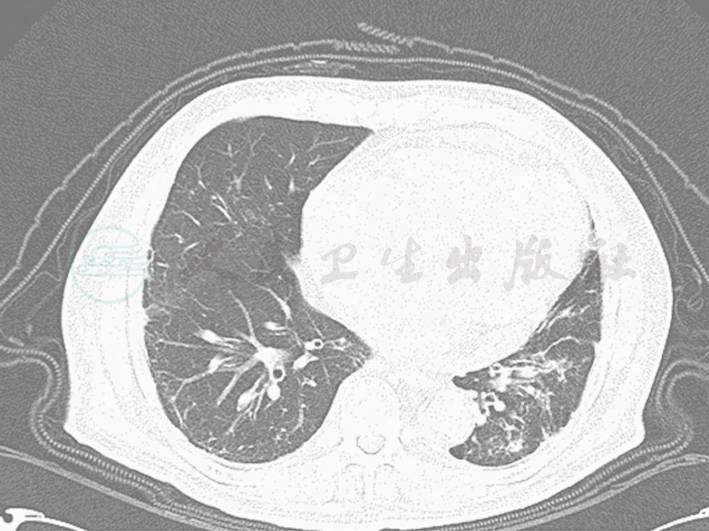

患者,男性,80岁,因“腹胀、腹痛9小时”于2010年10月26日就诊。诊断为不全性肠梗阻。既往有高血压、冠心病、心功能不全、慢性肾功能不全、脑梗死等病史,基础血肌酐200μmol/L左右。经过保守治疗肠梗阻好转,因血压控制不佳,血压维持在190/60mmHg于2010年10月30日转入老年科。入老年科后因“二度Ⅱ型房室传导阻滞”,行永久性起搏器植入术,血压控制在150/60mmHg。2010年11月17日出现发热,伴咳嗽、咳痰,肺部听诊左下肺可闻及少量湿啰音,血常规:WBC 5.67×109/L、中性粒细胞80.4%。行胸部CT提示支气管扩张合并感染(图1)。予以哌拉西林钠-他唑巴坦钠抗感染治疗,但一直存在低热、咳嗽、咳痰,并于活动后出现胸闷、气喘。复查肾功能,血肌酐上升至350μmol/L。加用莫西沙星,但病情无好转,出现胸闷、气喘加重,小便量减少,转科前当天白天的小便量仅为100ml,肌酐上升至588μmol/L,2010年11月28日转入ICU。

图1 胸部CT提示:支气管扩张合并感染